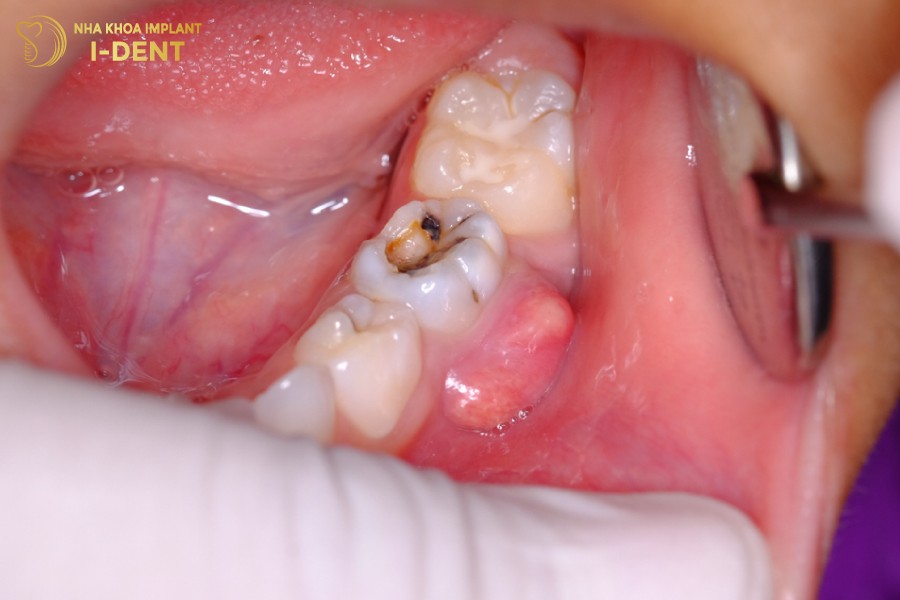

- Răng bị sâu nặng, không được kiểm soát làm tủy bị viêm nhiễm, dần dần hình thành ổ mủ quanh chân răng do vi khuẩn phát triển ồ ạt.

Mảng bám vôi răng là nguyên nhân hàng đầu gây viêm tủy răng